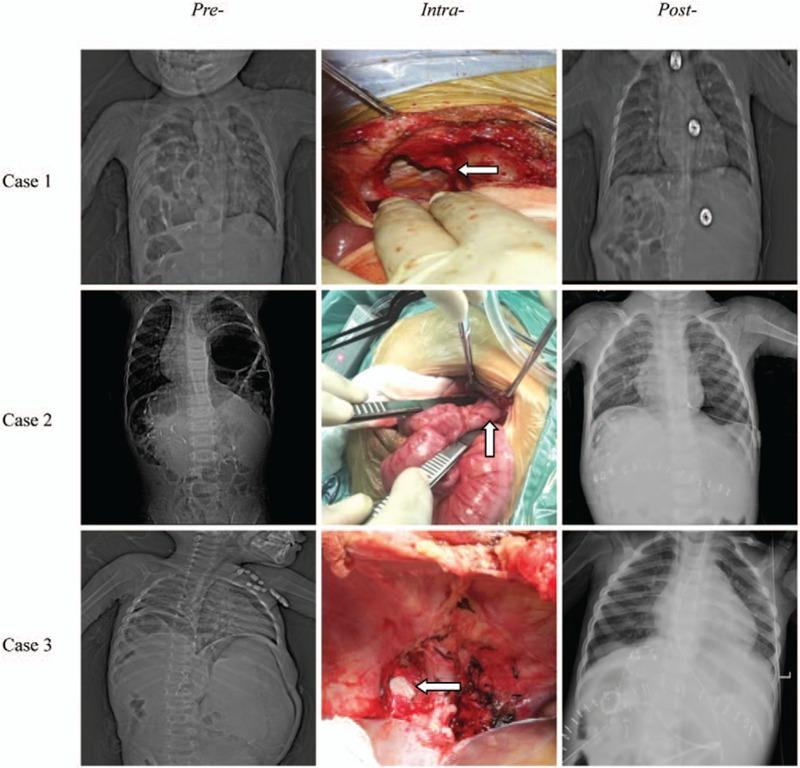

Acquired diaphragmatic hernia in pediatrics after living donor liver transplantation: Three cases report and review of literature.

The primary disease was biliary atresia and DH was diagnosed by computed tomography scan or x-ray of chest.

Laparotomy was performed successfully to repair the DH.

The respiratory and digestive function was gradually recovered in 1 to 2 weeks after repair operation. In 2 to 8 months follow-up, patients were asymptomatic without any respiratory or digestive complications.